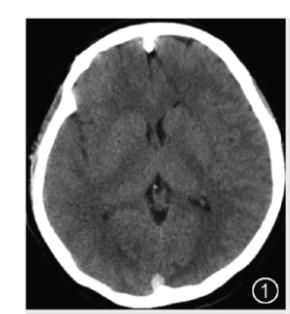

①CT平扫

I.直接征象:静脉窦内三角形或条带状高密度影。当血栓位于大脑皮层浅静脉,可见条带状高密度影,即为“束带征”(图2)。当血栓位于上矢状窦后部,表现为圆点或者三角状高密度影,即为“三角征”(图3)。

图3 CT平扫提示上矢状窦类圆形高密度影,即三角征II.间接征象:包括脑水肿、脑梗死或颅内出血等。